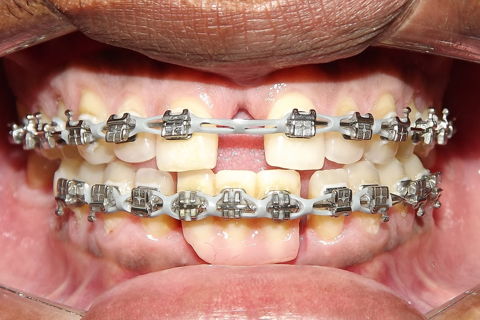

fotos finais, paciente encaminhado para implantes.

Paciente do sexo masculino, 36 anos, brauifacial. Relatava que os Diastemas lhe incomodavam muito, e em tratamento anterior o profissional fez exo de 2 incisivos centrais inferiores e instalou Prótese movel com 4 incisivos, após um tempo de uso a prótese começou a incomodar. em planejamento com o implantodontista ficou definido o fechamento dos diastemas e reabilitação dos elementos 41 e 31 com implantes.